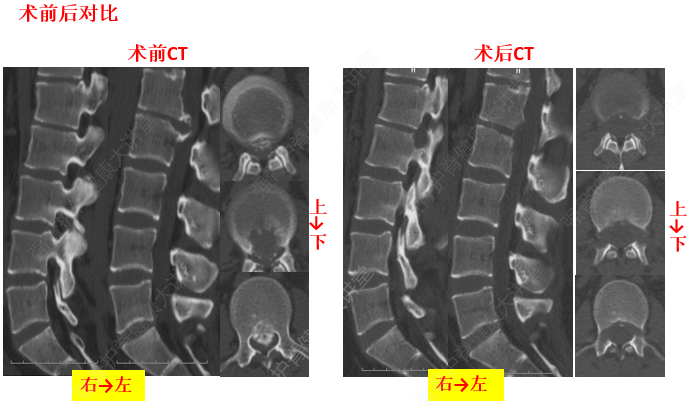

3、椎間盤與椎間韌帶的退變

椎間盤的退變是發(fā)生頸椎病的基礎既是產(chǎn)生本病的內因,又是其較為普遍的病理改變。如頸部的長期過度伸、屈活動可使弓間韌帶(發(fā)生相應的改變)變厚、彈力減弱,甚至發(fā)生鈣化或骨化,直接壓迫脊髓。長期過伸,可損傷前縱韌帶,突然的猛力后伸活動,可造成前縱韌帶與椎體前緣附著處的撕裂。反之,可造成后縱韌帶損傷或與椎體后緣附著處的撕裂。由于椎間盤的退變,首先出現(xiàn)韌帶松弛,繼而發(fā)生肥厚、鈣化或骨化反應。韌帶鈣化部位與椎間盤受損平面相一致。本病患者項韌帶的鈣化是普遍的,可在頸后觸及條索狀物。